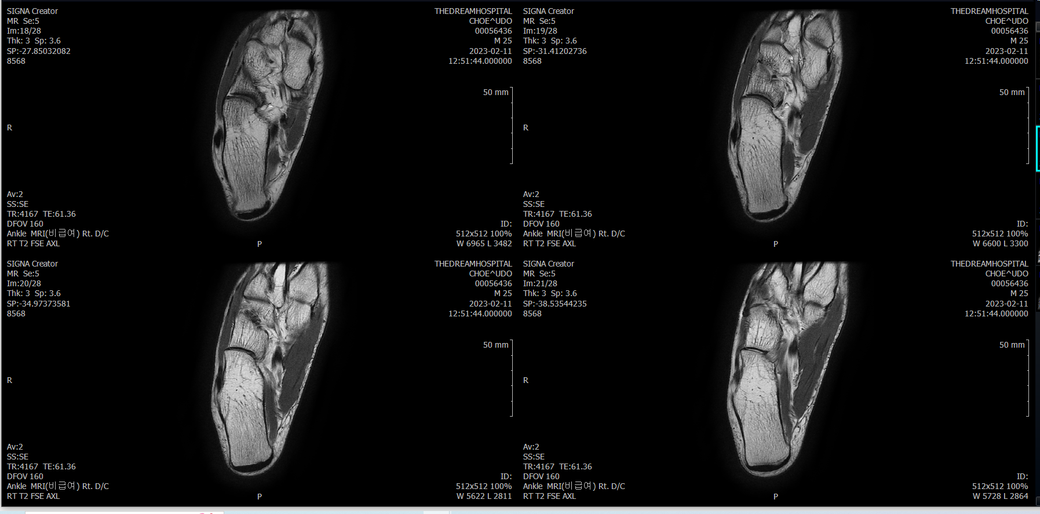

오른발목 mri 전체사진입니다. 제가 병원을 갈수없는상황인지라.... 봐주시면 감사하겠습니다.

엑스레이에서는 문제가 없다고 하여 오른발목 mri촬영했습니다.